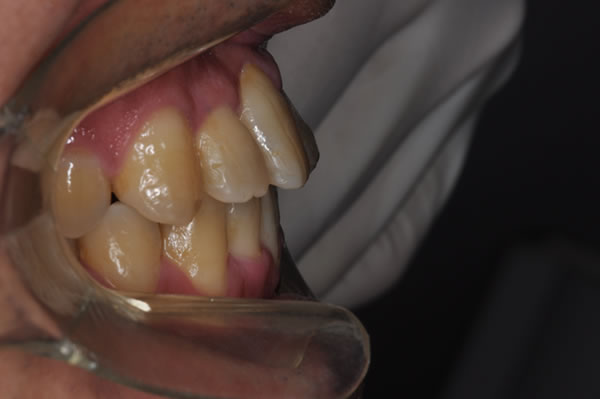

反対咬合症例

治療前(初診)